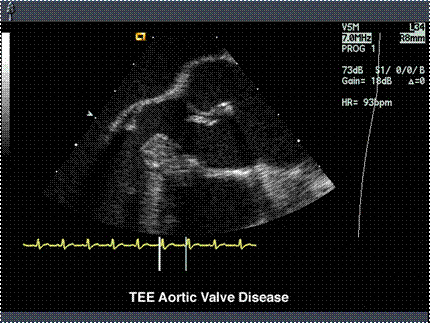

Echo realizeaza diagnosticul:

- inchidere precoce a valvei mitrale

- ruptura valvelor

- abces de inel

- jetul de regurgitare

- faldul in lumenul aortei (disectie)